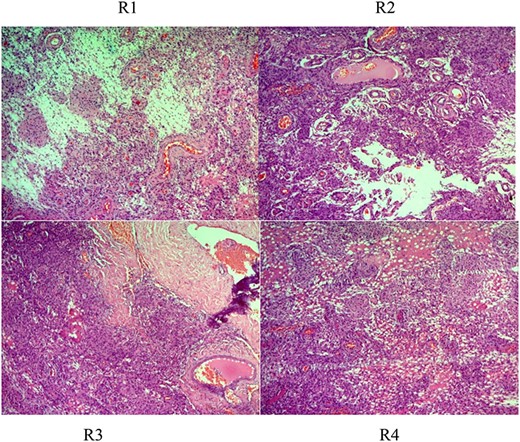

After surgery, the tumor at C5–C7 showed meningothelial meningioma (Fig. 3). The second tumor in the spine at C2–C4 was ependymoma (Fig. 4). Tumor in the brain showed rhabdoid meningioma (Fig. 5).

Histologic description of rhabdoid meningioma (brain) (WHO Grade II). R1–4 (H&E ×50, ×100, ×200): sheets of loosely cohesive cells with clear nuclei and pleomorphism, retaining meningothelial features (whorl formation).